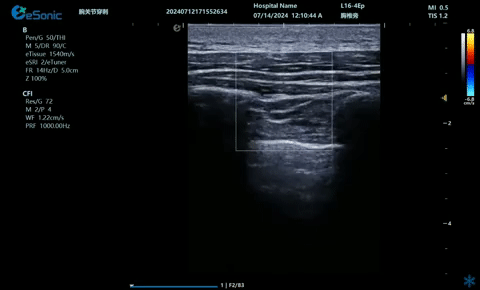

超声引导下肋间神经阻滞切面